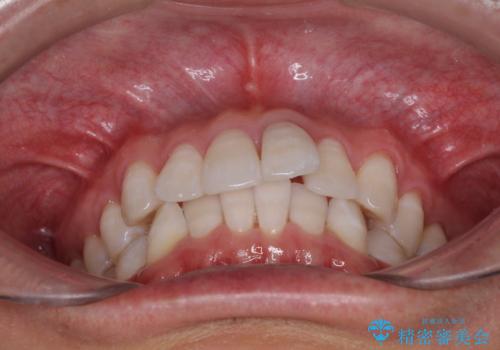

前歯のデコボコを治したい インビザラインによる矯正治療

- 前歯のデコボコを治したいとのことで来院された患者様です。

上下顎ともに歯列全体の後方移動とIPR(歯と歯の間を削る)によってデコボコが解消するように設計し、インビザラインにより治療を行うこととしました。